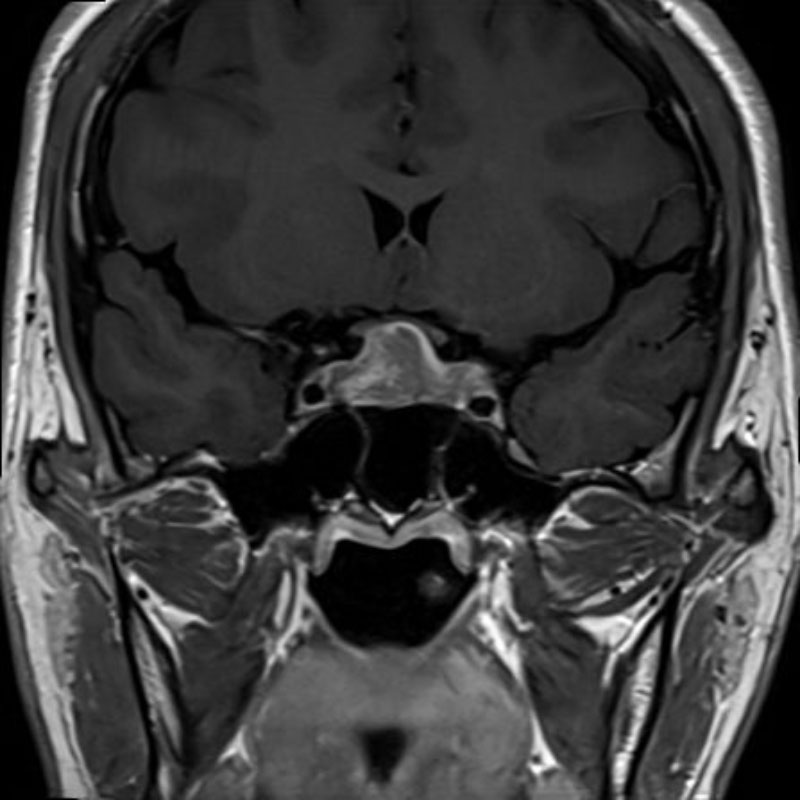

断層撮影

手術前1